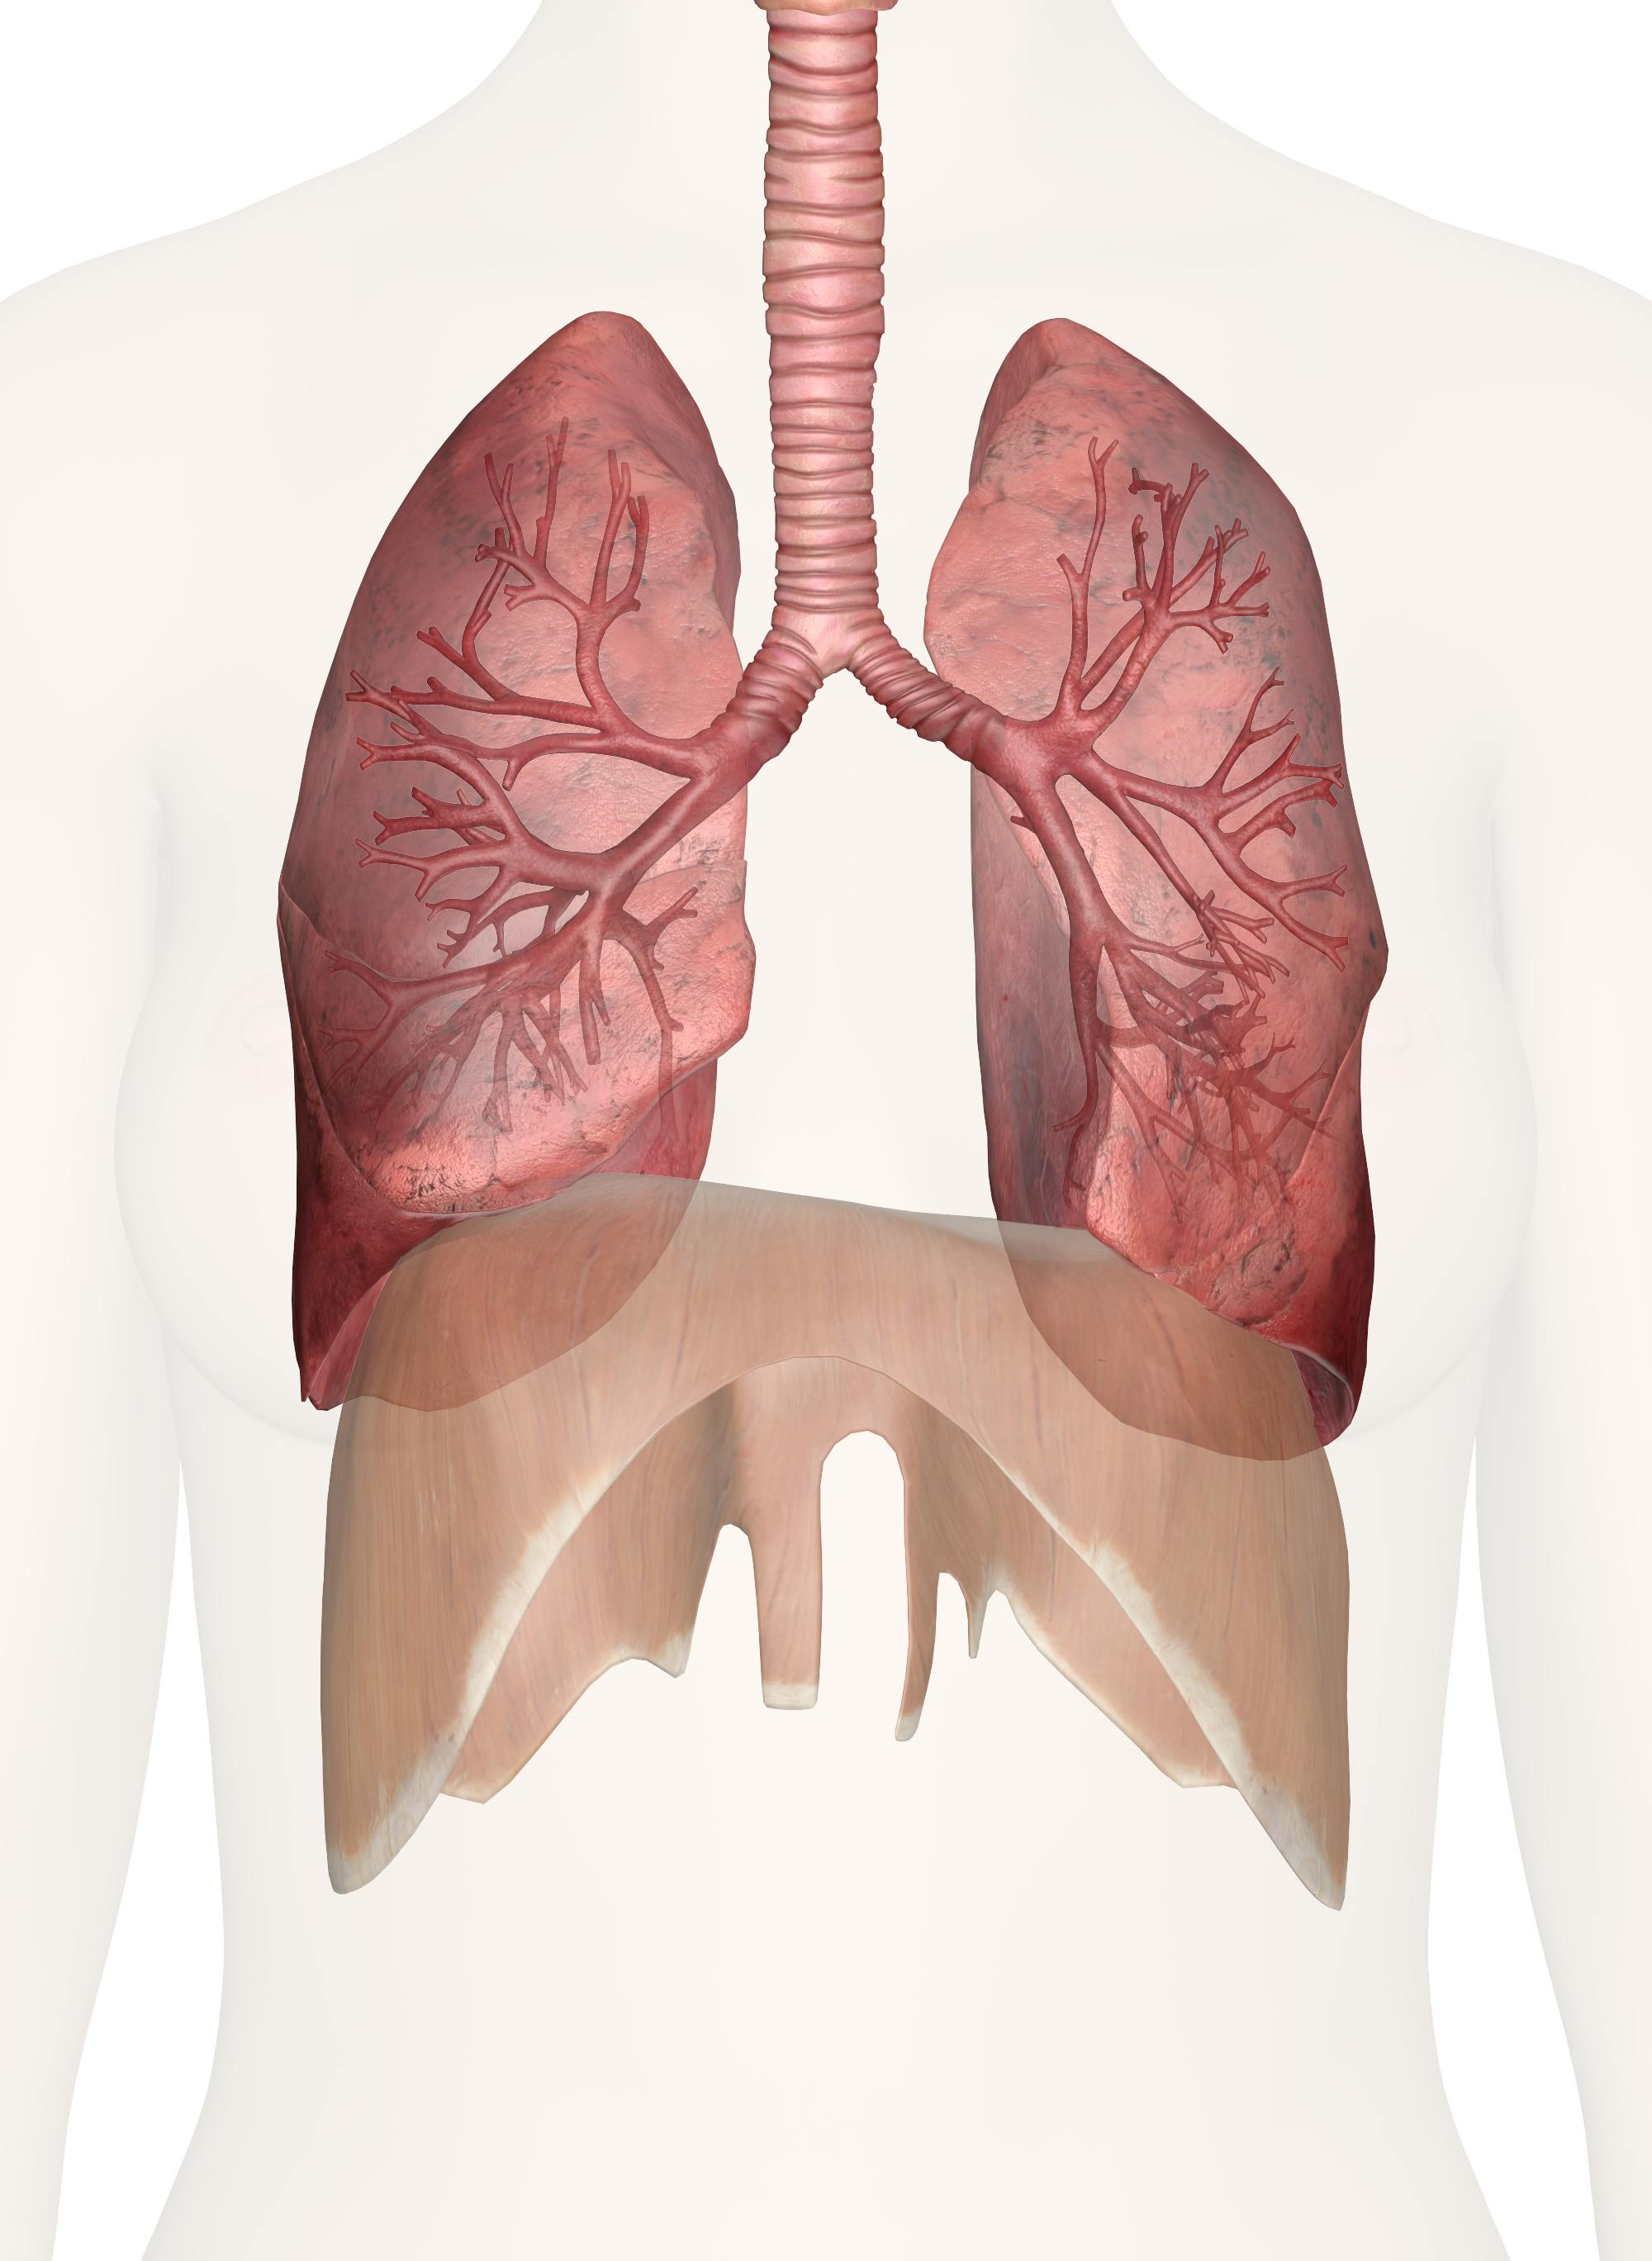

The human body is an intricate network, constantly sending signals about its internal state. Our lungs, vital for breathing and oxygenating the blood, can unfortunately develop diseases silently, often without obvious symptoms until an advanced stage. This reality makes understanding subtle, often overlooked, bodily clues paramount, particularly those that manifest on our hands and fingernails.

This distinctive alteration is frequently associated with chronic lung diseases such as chronic obstructive pulmonary disease (COPD), various forms of lung cancer, and pulmonary fibrosis. The primary physiological driver behind finger clubbing is often reduced oxygen levels in the blood. This lack of adequate oxygen prompts specific changes in the soft tissues at the fingertips, leading to their characteristic enlarged and rounded appearance, a process involving hypoxia and increased growth factors. A simple self-check, the “Schamroth sign,” involves placing corresponding nails together; the absence of a diamond-shaped window may indicate clubbing, warranting professional assessment.

2. **Cyanosis (Bluish Discoloration)**Cyanosis, identifiable by a distinct bluish tint on the nails, skin, or lips, is a critical warning sign that your body is not receiving sufficient oxygen. This visible discoloration directly signals low oxygen levels in the blood, known as hypoxemia. When oxygenated blood is plentiful, these areas appear pink; however, as oxygen saturation declines, the blood takes on a darker, bluish hue, becoming apparent through the skin.

In the realm of lung health, cyanosis serves as a direct indicator of diseases that severely impair oxygen absorption. Conditions like pneumonia, chronic bronchitis, and severe asthma attacks commonly lead to this symptom. These infections or inflammatory states can cause the lungs to fill with fluid or mucus, or constrict airways, preventing adequate oxygen from entering the bloodstream. The bluish tint is a stark visual alert that the respiratory system is struggling significantly.

The provided context explicitly links the widening of fingers and clubbing of fingernails to pulmonary fibrosis, a severe and progressive type of lung disease. Pulmonary fibrosis causes scarring in the lungs, making them stiff and significantly impeding breathing function. The body’s response to diminished lung efficiency and compromised oxygen exchange can lead to these changes in the extremities, establishing thickened fingers as a crucial clinical indicator for respiratory specialists.